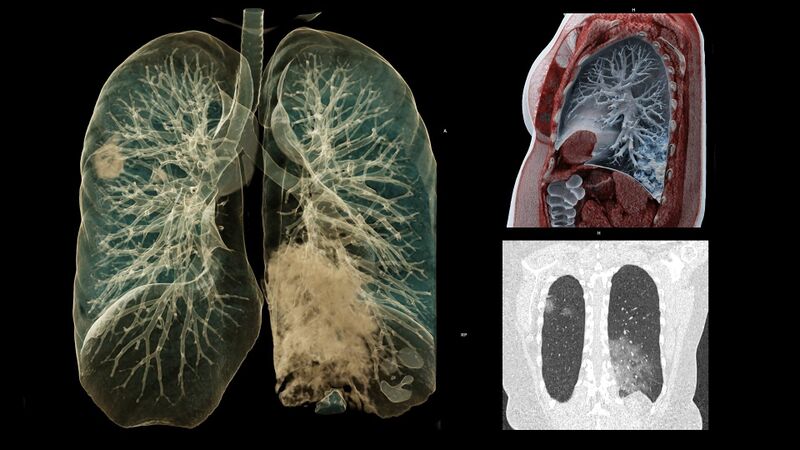

Vaizdas:Covid-19-ilgalaikiai-plauciu-pazeidimai.jpg